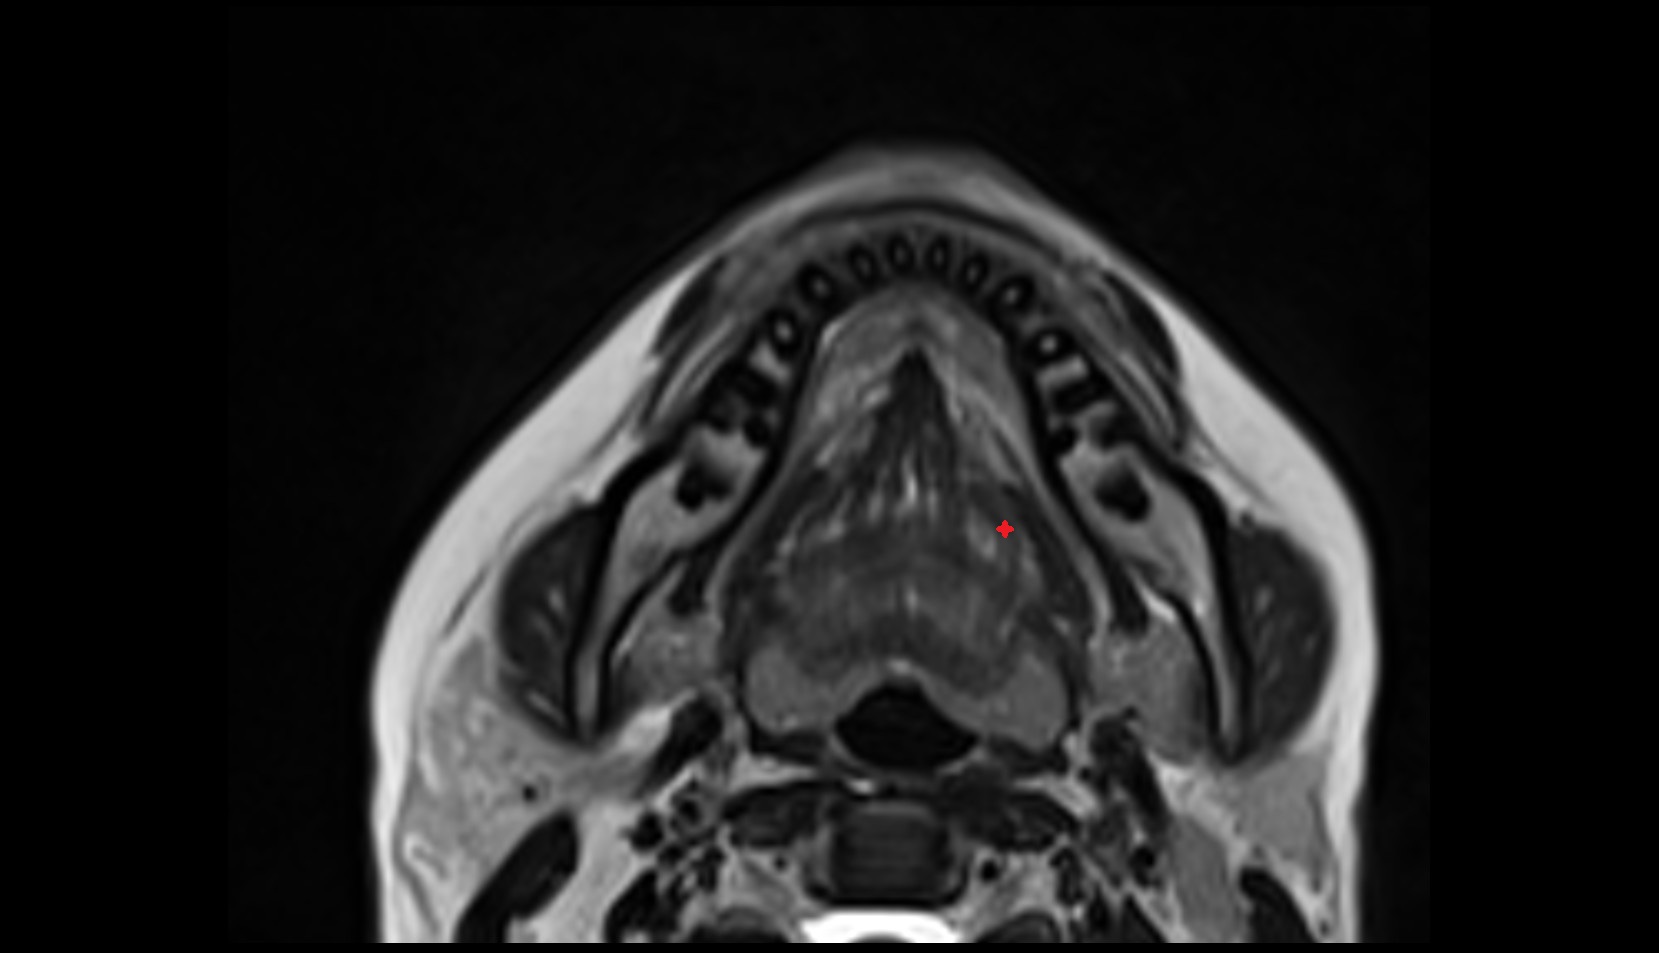

- Temporomandibular joint

- Mandibular condyle

- Mandibular fossa

- Articular disc of temporomandibular joint

- Articular eminence

- Superior head of lateral pterygoid muscle

- Inferior head of lateral pterygoid muscle

- Lateral pterygoid muscle

- Masseter muscle

- Medial pterygoid muscle

- Temporalis muscle